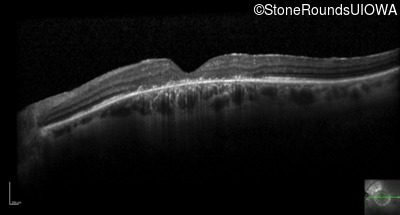

Optical Coherence Tomography - Right - 20/60 sc

Exemplar / OCT Stack